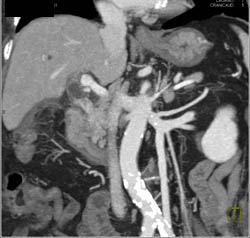

Bleed in and Near Liver S/p Stab Wound